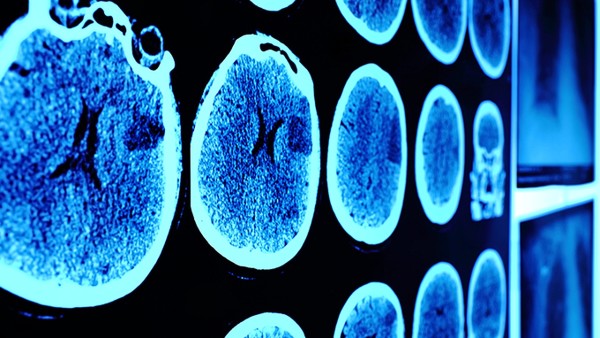

脑梗塞溶栓通过静脉用药,疏通血管中的栓剂,使血管再次畅通,是目前早期治疗脑梗塞的常用方法。一般建议发病不超过3小时的患者治疗。80岁以上的老人、器官衰竭、最近接受手术的患者不能进行溶栓治疗。